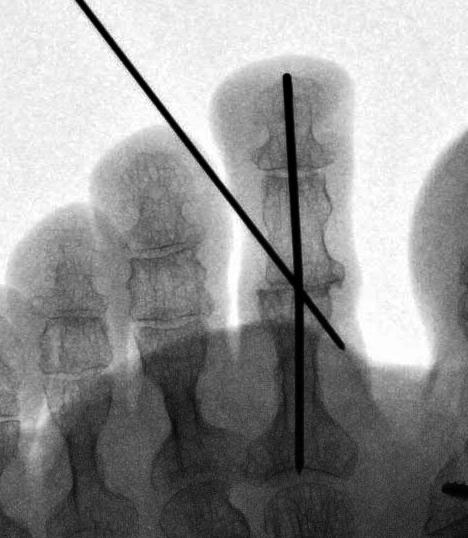

• Belastete Aufnahmen des Fußes in zwei Ebenen (dorso-plantar und lateral) sind hilfreich um das frontale und sagittale Alignement der Zehen zu beurteilen. Zudem ist auf eine eventuell bestehende Luxation bzw. Subluxation des MTP-Gelenkes zu achten.

• Eine Röntgenkontrolle wird 6 Wochen postoperativ durchgeführt (Fuß belastet in zwei Ebenen). Besonders geachtet wird auf eine knöcherne Konsolidierung der Arthrodese und auf die Lage eines gegebenenfalls verwendeten intramedullären Implantats.

• Persistierende Fehlstellungen sind der häufigste Grund für Patientenunzufriedenheit 123. Diese können sowohl in der sagittalen, frontalen und transversalen Ebene auftreten.